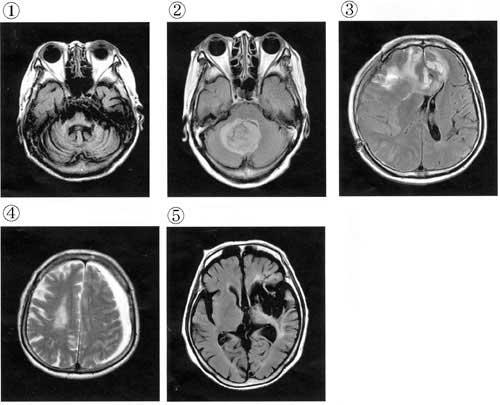

38歳の男性。30歳ころから歩行時にふらふらする感じを自覚していた。最近、階段昇降で手すりが必要となり、構音障害と上肢の協調性低下も出現した。症状が徐々に進行し、屋内つたい歩きとなったため入院した。意識は清明。知能は正常である。感覚障害はなく、病的反射も認めない。兄も同様の症状を呈している。MRI(写真①~⑤)を示す。この症例はどれか。

1

①

2

②

3

③

4

④

5

⑤